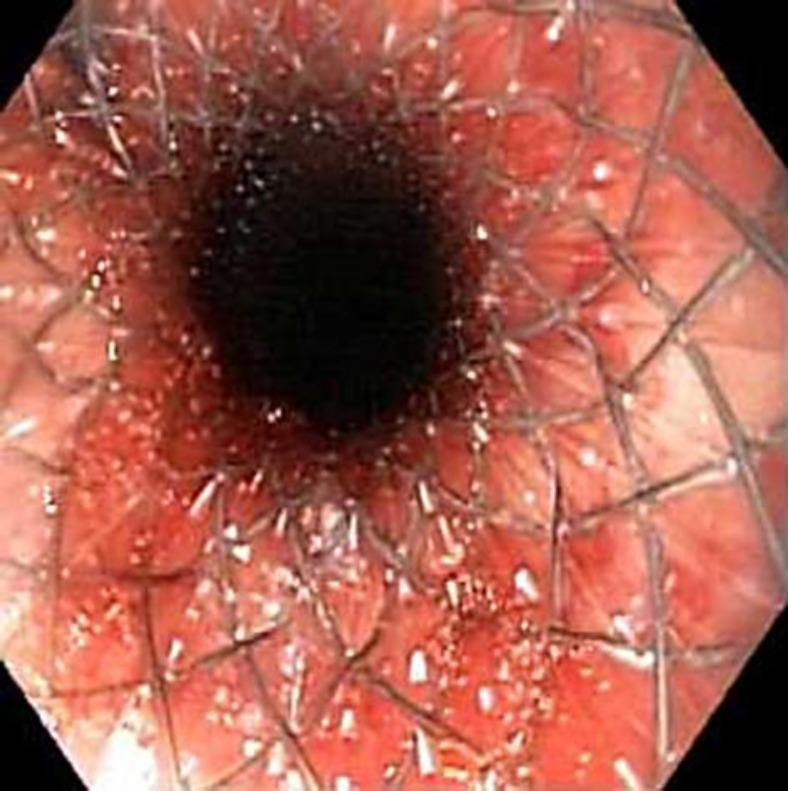

Transesophageal echocardiography (TEE) is a commonly used procedure in patients with suspected endocarditis. A rare but dreadful complication of this procedure is perforation of the esophagus. We report the case of an elderly female with multiple comorbidities, who presented with polyarticular septic arthritis. TEE was performed to rule out endocarditis. Though the standard procedure protocol was followed, she developed esophageal perforation. It was managed with esophageal stenting but she developed multiorgan failure and did not survive. This case highlights the potential of severe morbidity and mortality associated with TEE. Appropriate screening must be done and high-risk individuals must be identified before such procedures are attempted.

经食管超声心动图(TEE)是疑似心内膜炎患者常用的检查方法。该检查罕见但严重的并发症是食管穿孔。我们报告了一例患有多种合并症的老年女性病例,她因多关节感染性关节炎就诊。进行TEE以排除心内膜炎。尽管遵循了标准的操作流程,但她仍发生了食管穿孔。采用食管支架置入术进行治疗,但她出现了多器官功能衰竭,最终未能存活。该病例凸显了TEE相关的严重发病和死亡风险。在尝试此类检查之前,必须进行适当的筛查并识别高危个体。